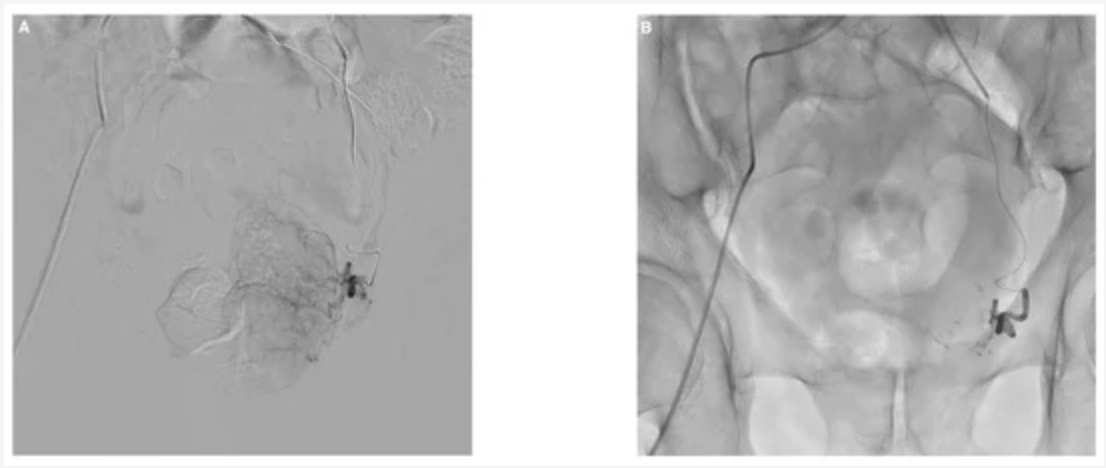

A study about Prostate Artery Embolization Using N-Butyl Cyanoacrylate Glue for Urinary Tract Symptoms Due to Benign Prostatic Hyperplasia.

A study about Prostate Artery Embolization Using N-Butyl Cyanoacrylate Glue for Urinary Tract Symptoms Due to Benign Prostatic Hyperplasia.